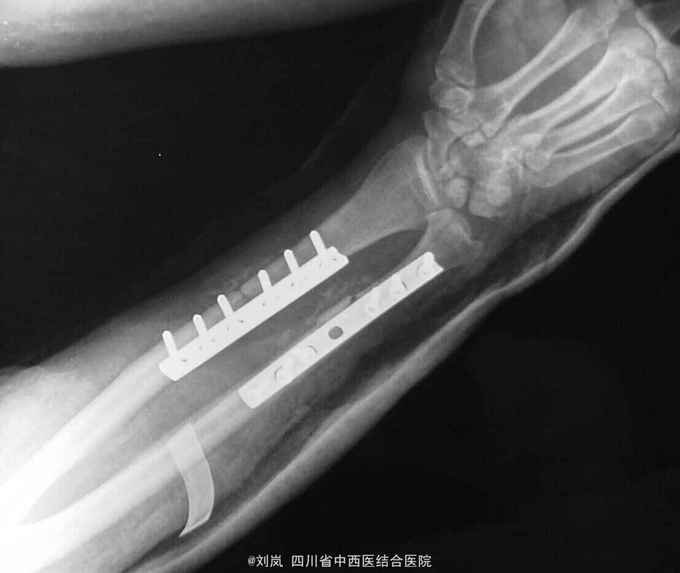

入院诊断: 1、高处坠落伤 2、脑挫裂伤 3、小肠部分坏死 小肠穿孔 肠系膜挫伤 4、右肱骨中段骨折 5、右尺桡骨中下段骨折 6、腹腔积气 7、右第7、8肋可疑骨折 8、轻度贫血 9、全身多发皮肤软组织挫伤 转入诊断: 1、高处坠落伤 2、右肱骨中段骨折 3、右侧尺桡骨中下段粉碎性骨折 4、脑挫裂伤(右,顶叶) 5、右侧桡神经损伤 6、右侧正中神经损伤 7、右侧尺神经损伤 8、右前臂Volkmann缺血性肌痉挛 9、右侧第7肋、左侧第8肋骨骨折 10、小肠部分切除、小肠修补、阑尾切除术后 11、右膝清创缝合术后 12、腹腔积气 13、轻度贫血 14、全身多发皮肤软组织挫裂伤 治疗: 患者急诊入院后,予完善检查,诊断明确,完善急诊手术准备,急诊在全麻下行了“剖腹探查:小肠坏死部分切除、小肠修补+阑尾切除术+腹腔引流术”,术后在ICU继续抗炎、止血、补液脱水监护对症治疗,并请骨科会诊后予右上肢石膏固定。 术后两周外科病情平稳,再次请骨科会诊后转骨科治疗。转入后进一步完善相关检查及术前准备,诊断明确后,在“全麻”下行了"右肱骨中段骨折切开复位内固定、右尺桡骨中下段骨折切开复位内固定术+植骨术、右侧桡神经损伤探查术",术中见桡神经挫伤明显,局部瘀血及增生组织包裹,予松解处理。术后予消肿、止痛、营养神经、预防感染等对症支持治疗,结合针灸、理疗、中药口服及康复治疗。术后伤口愈合及拆线后,予中药熏洗治疗,配合患肢主被动功能康复锻炼,住院2个月,患肢功能活动明显改善,病情好转出院。

随访:出院后定期复诊治疗,继续予药物营养神经、门诊针灸及中药治疗,术后6个月患肢感觉基本恢复正常,功能活动明显改善。 讨论:该患者损伤部位多,创伤重,并发症多,故治疗方案复杂,根据病情需要随时调整治疗重点及治疗方案。神经损伤病情判断及手术探查指征、时间如何把握?